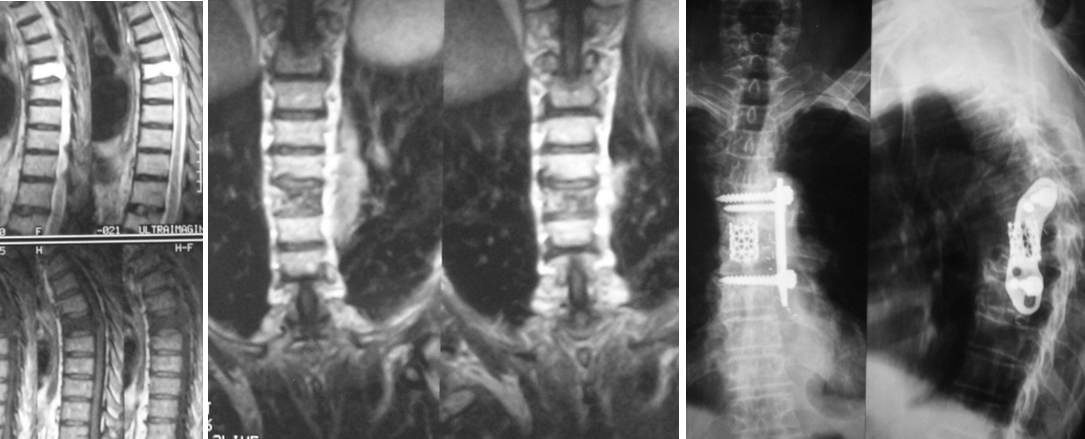

Ողնաշարային սկավառակների ճողվածքների բուժումը ներկայում իրականացվում է միկրովիրահատական եղանակով: Պարանոցային հատվածի ճողվածքների դեպքում հեռացվում է ախտահարված սկավառակը և փոխարինվում ինքնաամրացվող քեյջով:

|

Ողնաշարի պարանոցային հատվածի ճողվածք |

Վիրահատական շտկումից առաջ Վիրահատական շտկումից հետո

Ողնաշարային խողովակի ստենոզի (նեղացման) ժամանակ ողնուղեղն ազատելու նպատակով հեռացվում են ողերի հետին տարրերը և, ինչպես նրանց անկայունության ժամանակ, իրականացվում է ողնաշարի տրանսպեդիկուլյար ամրացում:

Ողնաշարի գոտկային հատվածի ողերի անկայունություն և ողնաշարային խողովակի ստենոզ |